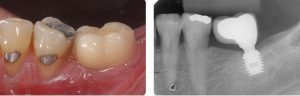

Possuímos a última tecnologia em implantes curtos, que são os implantes de 4mm de comprimento da empresa suíça Straumann, que é a empresa líder mundial em tecnologia e pesquisa em implantes dentários. Para a instalação desses implantes, a altura óssea pode ser bem baixa. Se a mordida e a oclusão do paciente permitirem, podem ser usados sem problemas. Isso evita muitos transtornos com enxerto ósseos, ganhando rapidez a praticidade na cirurgia.

Implante curto clinica e radiograficamente